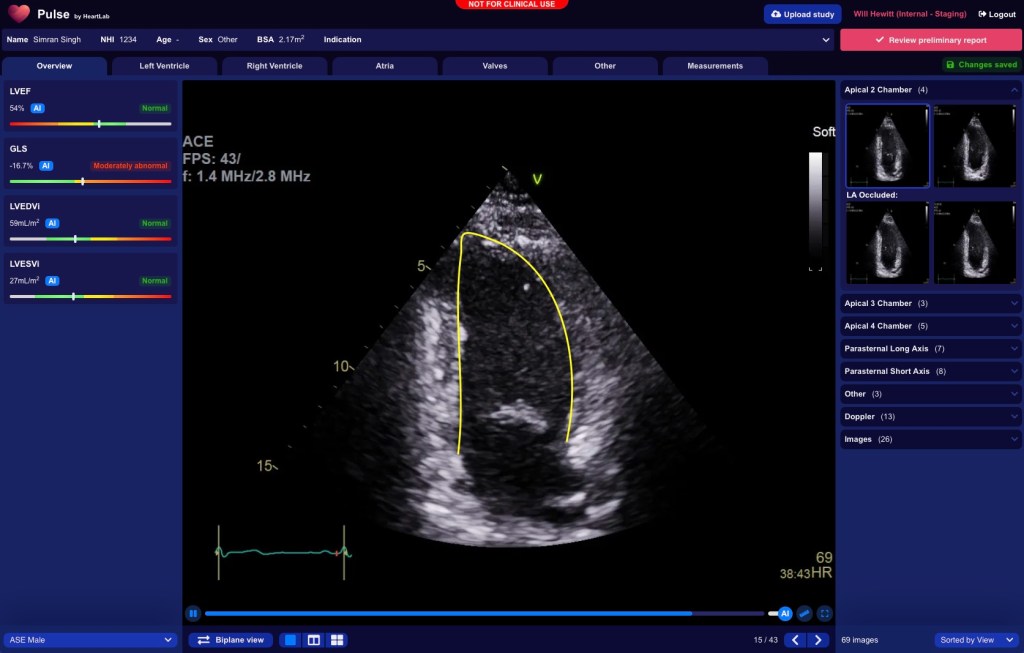

Image Credits:HeartLab

HeartLab provides an end-to-end solution for echocardiograms, the ultrasound tests that doctors use to examine a patient’s heart structure and function. Not only does the software help sort and analyze ultrasound images to help doctors diagnose cardiovascular disease, but it also streamlines the workflow by generating patient reports for doctors that can then be added to a patient’s health record.

Once HeartLab was able to successfully replicate the scanning process, the company worked to expand its services in a way that would relieve doctors of further admin minutiae so they could spend more time actually treating their patients. Usually, doctors use a software tool that analyzes the images, another that visualizes patterns and another that actually writes up the report, says Hewitt. HeartLab’s platform, called Pulse, can now condense those processes into one software.